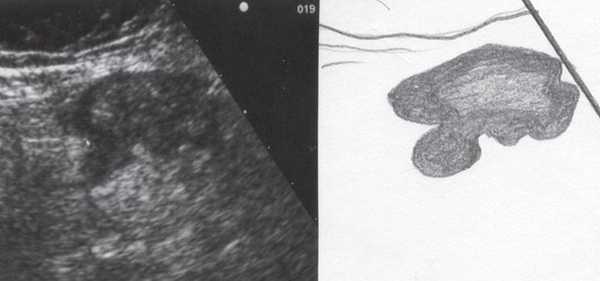

При трансвагинальном УЗИ (рис. 4) также визуализировался фрагмент толстой кишки с утолщенными гипоэхогенными стенками и несколькими округлыми дивертикулами до 1 см в диаметре. Контуры одного из дивертикулов были неровными, он имел звездчатую форму. Отмечались утолщение и повышение эхогенности околокишечной жировой клетчатки по сравнению с контралатеральной стороной. При осмотре в режиме УЗ ангиографии утолщенная стенка кишки и дивертикулы были аваскулярными, окружающая клетчатка - гиперваскулярной.

Рис. 4. Эхографическая картина дивертикулита. Трансвагинальное исследование конвексным датчиком 7,5 МГц.